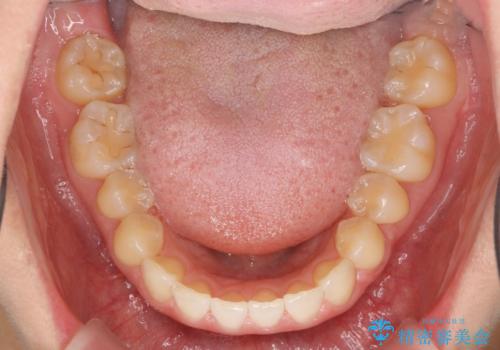

前歯のガタつきをきれいに マウスピース矯正治療

- 「前歯のガタつきをきれいにしたい。」と矯正治療を希望され来院されました。

前歯のガタつきをワイヤー部分矯正、上顎前突の咬合関係を後方移動することで理想的な咬合関係を確立します。

上顎の全体的な後方移動を実現するためにマイクロインプラントを併用したゴムかけを行ったことで理想的な咬合関係を確立することができました。